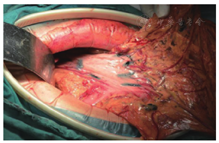

3.淋巴结示踪技术:开腹探查,显露肿瘤位置。使用1 ml注射器分两个区域注射纳米碳混悬液(卡纳琳,重庆莱美药业有限公司,每支0.5 ml:25 mg,生产批号:Z160806)。第一区域:距肿瘤边界2 cm处选取4点于浆膜下,每点0.1 ml左右纳米碳混悬液;第二区域:于胃体大小弯侧各选2~4点作为注射点,注射部位需避开肿瘤区域,每点注射0.1 ml左右纳米碳混悬液(图1)。对注射部位出现纳米碳渗出者,使用纱布轻压擦拭。纳米碳注射完成后10~15 min开始进行手术切除。

两组患者手术均顺利完成,无术中并发症。观察组患者均顺利完成纳米碳注射,未有误入血管者,总注射时间1~3 min。胃周淋巴结在注射纳米碳混悬液后3~5 min开始显影,10~15 min后可见NO.7至NO.12淋巴结出现黑染淋巴结,随着时间延长,黑染淋巴结范围逐步扩大。观察组手术时间(150±28)min,对照组手术时间(140±23)min,两组差异无统计学意义(t=1.790P=0.771)。观察组术中出血量为(207±121)ml,对照组术中出血量(256±182)ml,两组差异无统计学意义(t=-1.427,P=0.157)。